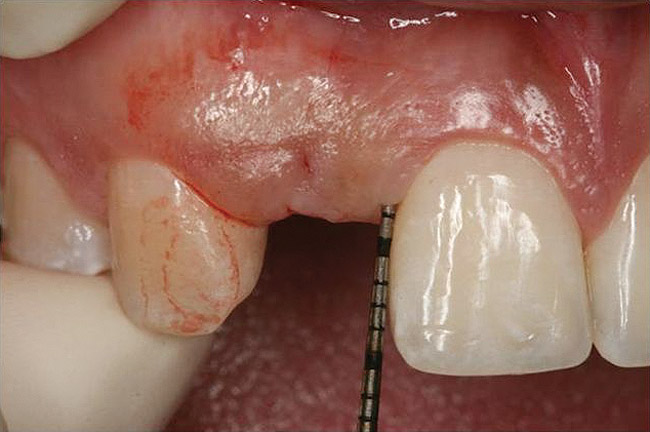

Figure 10  Clinical examination of the bound edentulous space: Measurement of the distal (Fig 10) and mesial (Fig 11) interproximal tissue height using a periodontal probe supplements data obtained from the periapical radiograph. Estimation of the buccal tissue thickness (bone sounding) is performed at the determined location of the gingival zenith using a guide developed from the diagnostic waxing (Fig 12).

Figure 10

Figure 11   Clinical examination of the bound edentulous space: Measurement of the distal (Fig 10) and mesial (Fig 11) interproximal tissue height using a periodontal probe supplements data obtained from the periapical radiograph. Estimation of the buccal tissue thickness (bone sounding) is performed at the determined location of the gingival zenith using a guide developed from the diagnostic waxing (Fig 12).

Figure 11